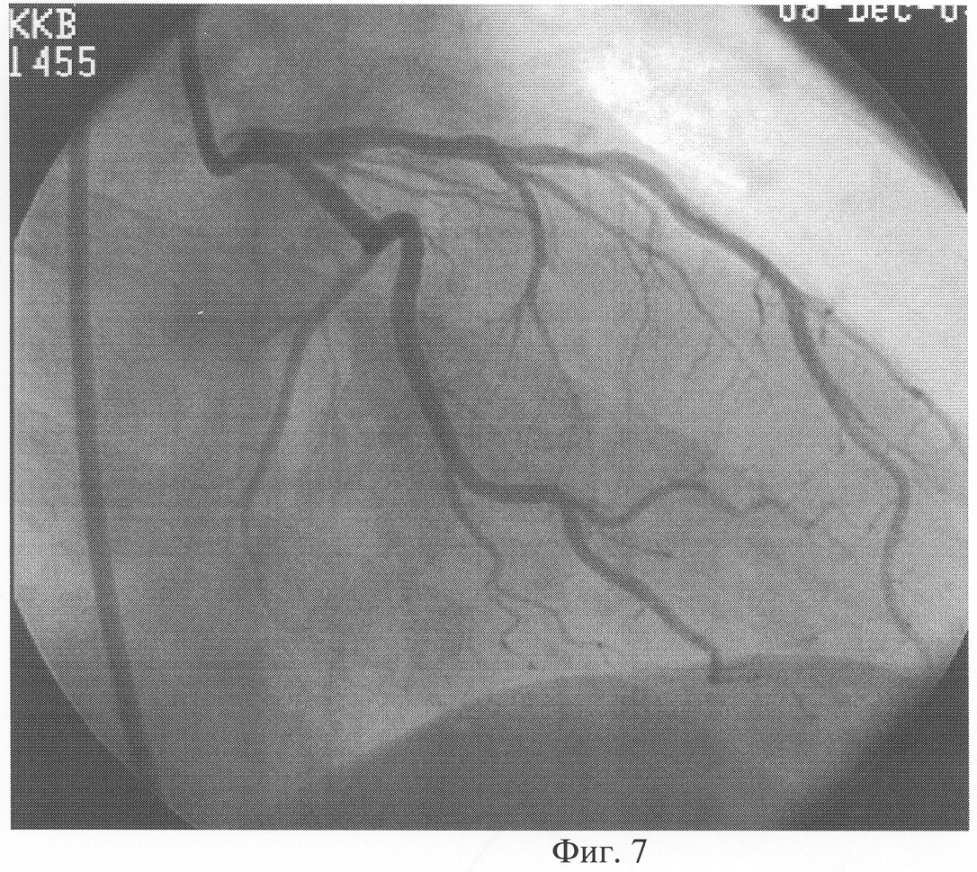

При проведении диагностики предлагаемым способом d равно 10,4% (d0=0,48 см, d1=0,53 см). После купирования симптомов бронхиальной обструкции проведена коронарография. По данным коронарографии правый тип кровоснабжения миокарда, коронарные артерии не изменены. При дальнейшем обследовании на МРТ выявлена грыжа диска Th3-Th4 грудного отдела позвоночника. Таким образом, диагноз ИБС не подтвердился.

Предлагаемый способ поясняется чертежами, где: на фиг.1 показан ультразвуковой датчик с изображением ОСА; на фиг.2 показан диаметр ОСА у больного ИБС (пример 1) до проведения ингаляции сальбутамолом; на фиг.3 – изменение диаметра ОСА после ингаляции сальбутамолом; на фиг.4 показан диаметр ОСА у пациента (пример 2) до проведения ингаляции сальбутамолом; на фиг.5 – изменение диаметра ОСА после ингаляции сальбутамолом; на фиг.6 приведена коронарограмма больного ИБС (пример 1); на фиг.7 – коронарограмма пациента (пример 2).